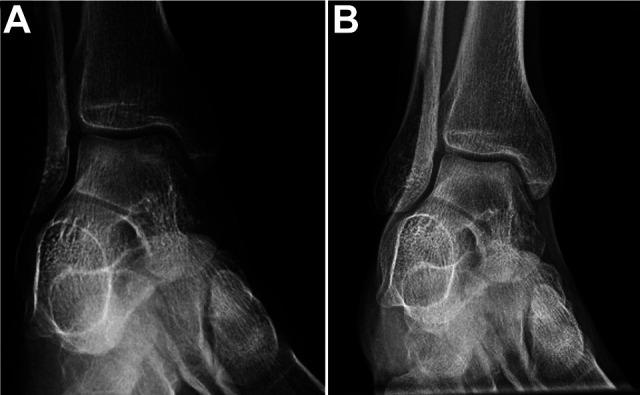

Predicting Outcomes of Talar Osteochondritis Dissecans Lesions in Children.

Reports detailing the rates of radiographic healing after treatment of talar osteochondritis dissecans (TOCD) remain scarce. There is also a paucity of data characterizing treatment outcomes and the risk factors associated with poor outcomes in children with TOCD.

The authors analyzed 92 lesions in 74 patients (mean age, 13.1 ± 2.7 years [range, 7.1-18.0 years]; 61% female). Of these, 58 (63%) lesions were treated surgically (drilling, debridement, microfracture, bone grafting, or loose body removal), and the rest were treated nonoperatively. Complete radiographic healing was seen in 43 (47%) lesions. In bivariate analysis, patients with complete healing were younger ( = .006), were skeletally immature ( = .013), and had a lower body mass index (BMI; < .001) versus those with incomplete healing. In a multivariate regression model, the factors that correlated significantly with the rate of complete healing were age at diagnosis, BMI, and initial surgical treatment. The lesion dimensions were not significantly associated with the likelihood of healing. A nomogram was developed using the independent variables that correlated significantly with the likelihood of complete radiographic healing.

Complete radiographic healing of TOCD lesions was more likely in younger patients with a lower BMI. The effect of initial surgical treatment on potential healing rate was greater in older patients with a higher BMI.